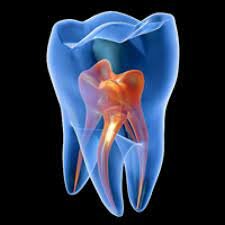

La endodoncia fue preacticada en el siglo I, cuando Arquígenes describe el tratamiento de pulpitis. Extirpación de la pulpa para salvar el diente

Vesalius, evidencia por primera vez la presencia de de una cavidad en el interior de un diente. Eustaquio señaló la diferencia entre dientes temporales y permanentes.